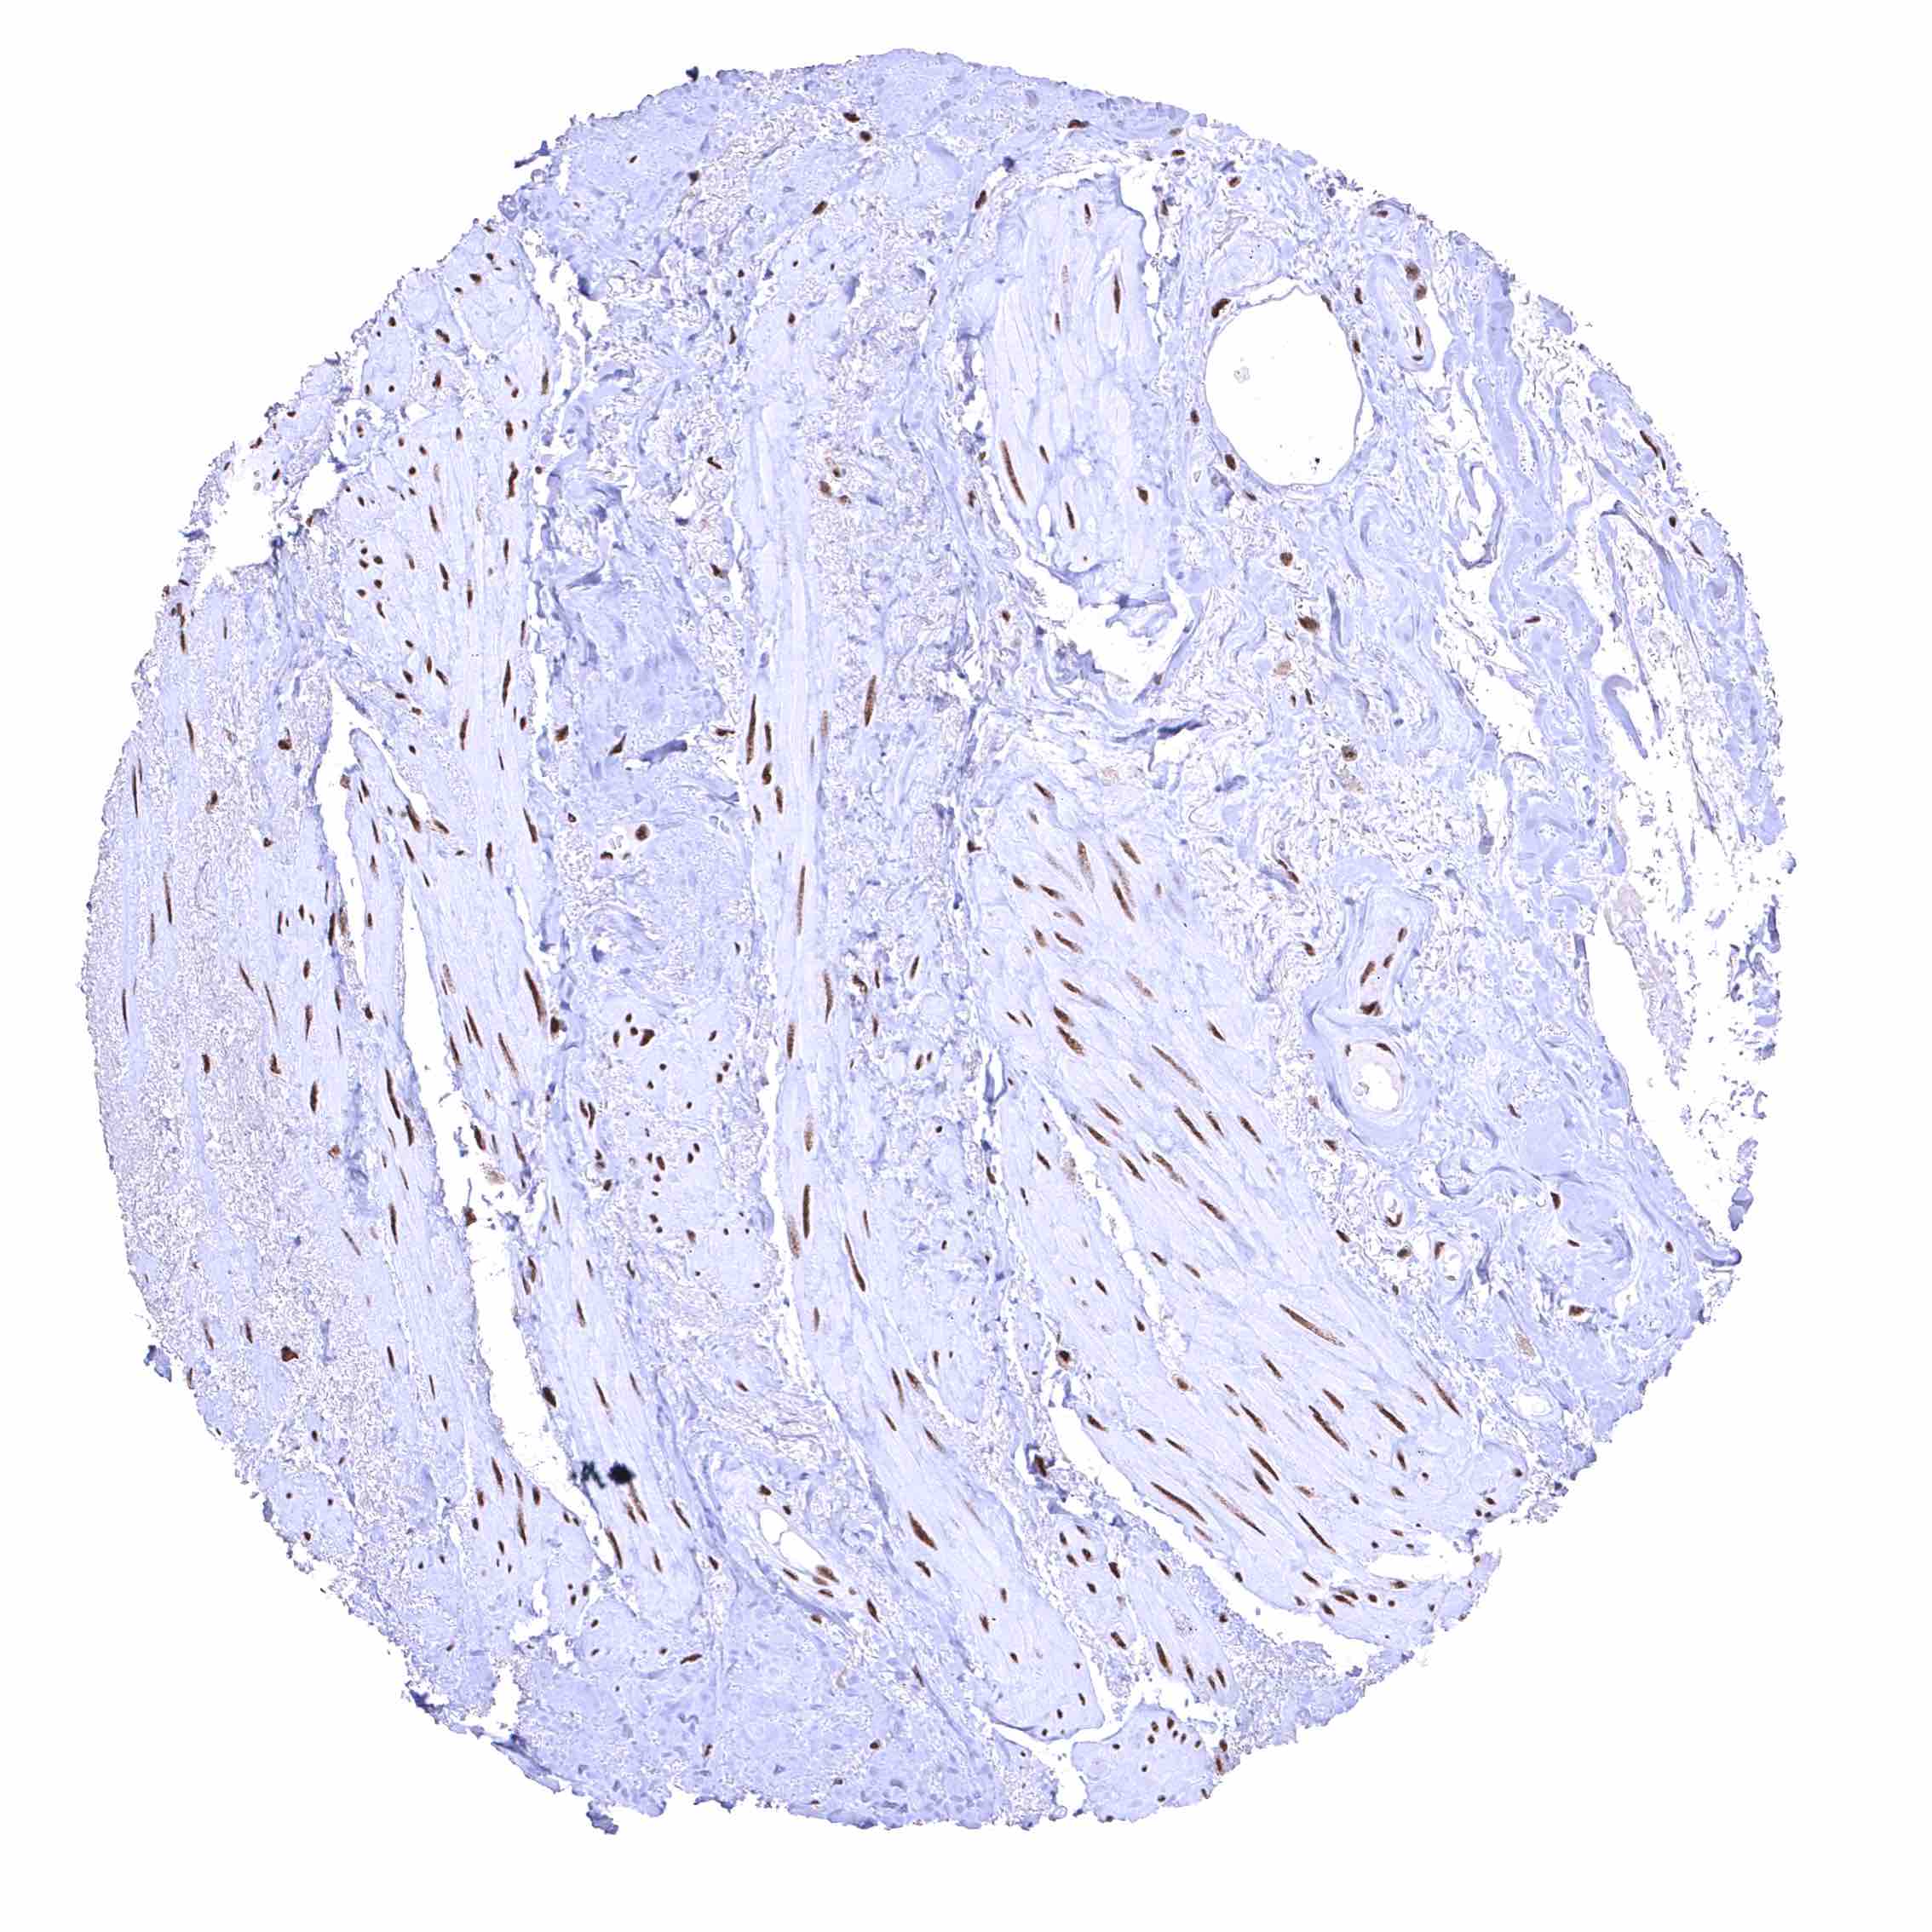

Uterus, myometrium – Distinct nuclear BRD4 staining of all muscle cells.